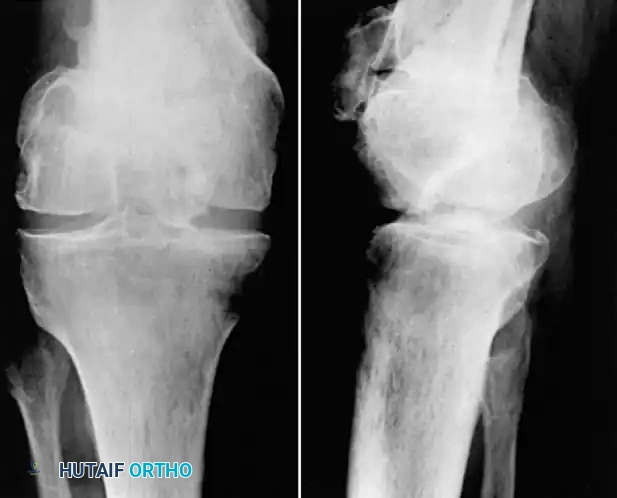

Fig. 55-16 Malunited comminuted fracture of both condyles of femur 1 year after injury. Knee motion was markedly limited and painful.

In young laborers or patients with active infection history, a compression arthrodesis is a highly durable salvage option.

Fig. 55-17 Same patient as in Figure 55-16, 3.5 months after compression arthrodesis. Knee is painless and stable for heavy labor.